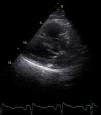

Por persistência do quadro clínico, apesar de antibioterapia instituída, foi realizado estudo complementar com Eco transtorácico. Apesar do exame ser limitado pela má janela acústica, este revelou: VE não dilatado com boa função sistólica global e segmentar; AE ligeiramente dilatada (área em plano apical quatro câmaras 22,8cm2); deficiente visualização dos folhetos da válvula mitral mas com abertura aparentemente conservada (Figura 1); aparente zona de isoconvergência na face auricular do plano do anel mitral, mas de difícil visualização por ecogenicidade aumentada a este nível; fluxo transmitral com gradiente diastólico máximo de 41mmHg e médio de 21mmHg (frequência cardíaca [FC] 104bpm); área valvular de 1,8cm2 calculada por tempo de hemipressão, sem regurgitação mitral associada; gradiente sistólico ventrículo direito (VD)/aurícula direita (AD) de 117mmHg, tendo sido excluída estenose pulmonar (Figura 2); cavidades direitas de tamanho e contratilidade conservadas.